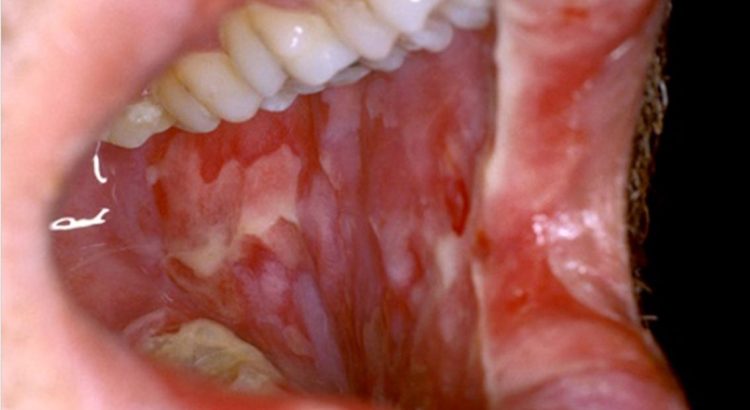

Lee Gay Lord – Oral mucositis adalah peradangan pada mukosa mulut yang ditandai dengan kemerahan, pembengkakan, dan luka yang nyeri. Penyakit ini umum terjadi pada pasien yang menjalani kemoterapi atau radioterapi, terutama terapi yang ditujukan ke area kepala dan leher. Oral mucositis bukan hanya mengganggu kenyamanan, tetapi juga dapat mempengaruhi kualitas hidup dan keberhasilan terapi kanker.

Gejala oral mucositis dapat berkembang secara bertahap, dan umumnya mencakup:

Meskipun bukan kondisi yang mengancam jiwa secara langsung, oral mucositis dapat berdampak besar pada pasien. Rasa nyeri yang hebat bisa membuat pasien tidak mampu makan, yang menyebabkan malnutrisi atau penurunan berat badan. Selain itu, jika tidak ditangani, luka dapat terinfeksi dan memperparah kondisi kesehatan.